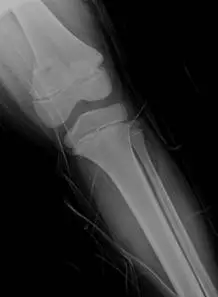

10 歲男童從滑梯跌落以左膝著地,由於膝部疼痛腫脹,父母帶他來急診求診,並接受 X光檢查,由此 X光影像,顯示他發生了何種的生長板傷害?

本題考的是兒童生長板骨折(physeal fracture)的 Salter-Harris 分類。10 歲男童從滑梯跌落以左膝著地,X 光影像顯示骨折線通過生長板(physis)並延伸至幹骺端(metaphysis),此為 Salter-Harris 第二型的典型表現。

影像一(側位,oblique view): 左膝關節 X 光側位,可見遠端股骨(distal femur)或近端脛骨(proximal tibia)生長板區域有骨折線。骨折線沿生長板水平走向,並伴隨一個三角形幹骺端骨片(metaphyseal corner fragment,又稱 Thurston Holland fragment),此為骨折線從生長板轉向幹骺端所造成的特徵性碎片。骨骺(epiphysis)本身結構完整,關節面未受波及。

影像二(正位,AP view,標記 L): 左膝正位影像,可更清楚看到骨折線同時涉及生長板與幹骺端的一角,骨骺端無明顯骨折線延伸,關節腔無明顯異常。整體影像符合骨折線通過生長板 + 幹骺端角落的 Salter-Harris 第二型特徵。